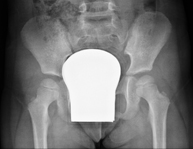

Procedimiento que permite, mediante el uso de rayos X, y tras inyectar un contraste en el interior de la articulación, detectar lesiones de determinadas articulaciones (cartílago, hueso, tendones, etc.) según la distribución del contraste. - RX Pelvis

Procedimiento mediante el cual, utilizando rayos X, se obtienen imágenes de la pelvis para su estudio, especialmente de los huesos pélvicos. - RX Edad ósea

Estudio que, utilizando los rayos X, permite obtener una imagen de los huesos de la cadera y descartar luxaciones. - RX Seriada ósea